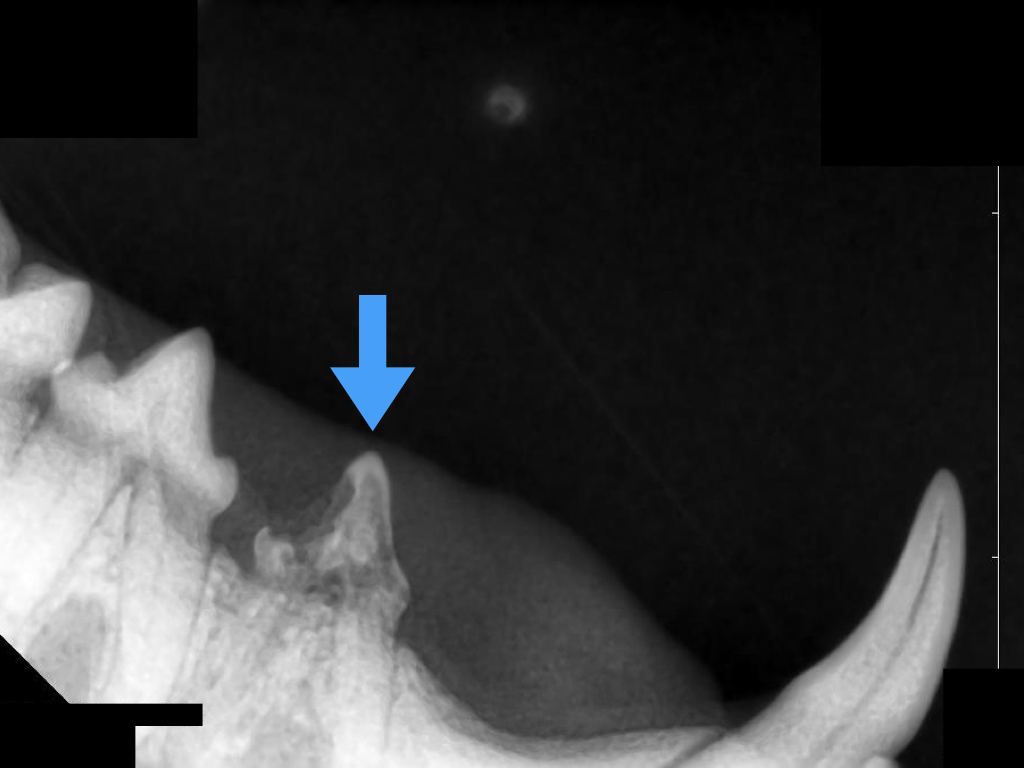

全身麻酔下でこの歯のレントゲン写真を撮ってみるとこのようになっています。

隣の健康な歯と比べると分かるように虫食い状に歯が溶けてしまっています。

これが破歯細胞性吸収病巣、通称“猫の虫歯”です。

この症例の歯はStage4aの吸収像が見られました。

この症例は写真左側の歯根はType2、右側の歯根はType1~2であり、Type3の治療を選択しました。